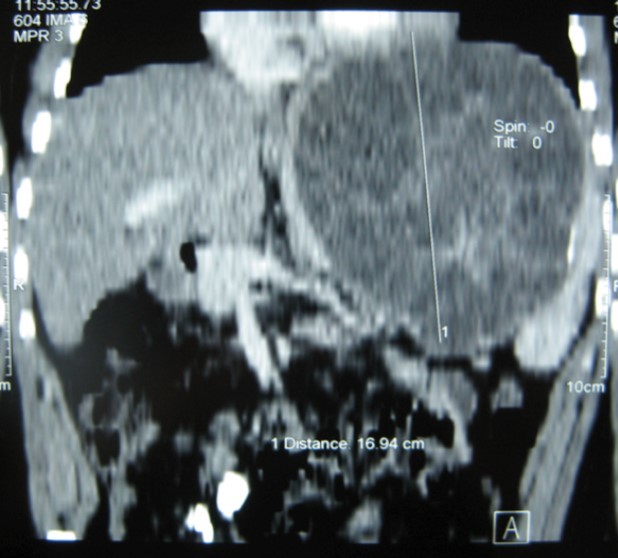

A 17-year-old young man admitted to our department with the complaint of abdominal pain localized in the left upper quadrant for the last 3 months. His physical examination revealed a splenomegaly. Immunoblot assay for Echinococcus was positive. His laboratory tests showed normal results of the serum and urine examinations, No eosinophilia was found. Chest X-ray revealed no pathological signs. An abdominal ultrasonography showed a 20 cm multivesicular cystic mass of spleen (figure 1). Contrast enhanced CT scans detected a huge single 20×16×18cm cystic mass located in the spleen. It had well-defined borders and contained multiple, round, daughter cysts in the periphery of the lesion with calcification (Figure 2, Figure 3, Figure 4). The patient underwent a laparotomy. A large splenic cystic mass was identified, attached to diaphragm, and tail of the pancreas (figure 5). The abdomen was packed with 10% hypertonic saline soaked pads in order to protect peritoneal soilage. A partial cystectomy without splenectomy was performed. Histologic examination of the specimen resection showed an echinococcal organism residing within the hydatid cyst . The patient was discharged after 4 postoperative days. 600 mg per a day of Albendazole therapy was instaured postoperatively and continued for 6 months. Two years after surgery the patient is well with disease free.

Figure 4.CT showing a huge single 20×16×18cm cystic mass located in the spleen

Ct scan is useful for diagnosis and screening, although there are a variety of pathognomonic signs of hydatid disease on imaging, they are not always present. Other cystic lesions of spleen, such as abscess, hematoma, or pseudocyst may be a diagnostic dilemma 5, 12. CT may show the cystic lesion with or without daughter cysts within the spleen with an attenuation value near that of water without any contrast enhancement 10, 11. Hematological examination may reveal eosinophilia. Immunoelectrophoresis, enzyme-linked immunosorbent assay (ELISA), latex agglutination, and indirect haemagglutination test are helpful for the diagnosis 13. A negative serology does not rule out cystic echinococcosis . In these cases the diagnosis can be difficult . Although the sensitivity of serological testing is not clearly dependent on the extent of disease, it does appear to be dependent on cyst stage. 14. echinococcal IgG ELISA test has perhaps the highest positive predictive value among the available serological tests, but unfortunately may only have a negative predictive value of <90% 14. A rapid immunochromatography test kit using the recombinant Em18 antigen was recently developed. It seems be simple, reliable, and easy-to-use 15.